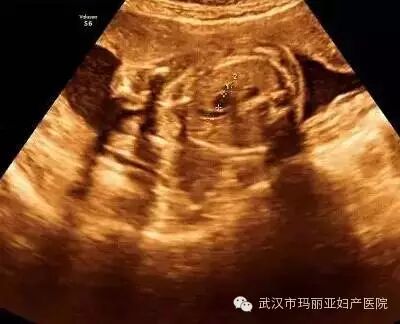

武汉玛丽亚妇产医院引进的世界领先的美国GE-E8四维彩超设备室目前世界上最先进、分辨率最高的彩色超声设备,具有即时立体成像、清晰准确的特点。

它能够多方位、多角度地观察宫内胎儿的生长发育情况,为早期诊断胎儿先天性体表畸形和发育异常提供科学依据。还能对胎儿的体表进行检查,如唇裂、脊柱裂、大脑、肾、 骨骼发育不良等,以便尽早的进行治疗。

玛丽亚美国GE-E8四维彩超排畸成功案例